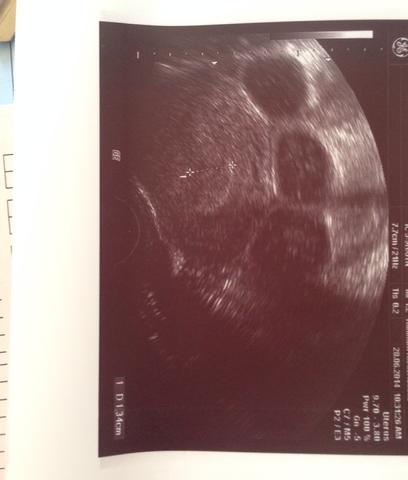

Jetzt bin ich schon heute 12 Tage drüber und weiss nicht ab wann ist ein Test wirklich sicher mit dem Ergebnis da ich ja 5 Tage. Eine optimal aufgebaute Schleimhaut zeigt im Ultraschall drei Linien. Proliferationsphase eine gut aufgebaute Schleimhaut hat zwei Bedeutungen.

Vielleicht kennst du schon meinen Artikel zum Aufbau der Gebärmutterschleimhaut hier und weißt deshalb dass eine gut aufgebaute Schleimhaut vor dem Eisprung mindestens 7 mm hoch sein sollte. FÄ sagt hoch aufgebaute schleimhaut nicht schwanger da ist eine Zyste die kann Hormone abgeben. Ich würde in der Zeit am liebsten gar nix testen oder messen oder sonst was. 3 Linien im Ultraschall. Entweder die baldige Mens oder eben eine SS. Ok dass ich am Eierstock eine Zyste habehatte wusste ich. Neben der Dicke der Schleimhaut ist aber besonders deren Aufbau wichtig. Man ist schwanger 2. Vielleicht kennst du schon meinen Artikel zum Aufbau der Gebärmutterschleimhaut hier und weißt deshalb dass eine gut aufgebaute Schleimhaut vor dem Eisprung mindestens 7 mm hoch sein sollte.